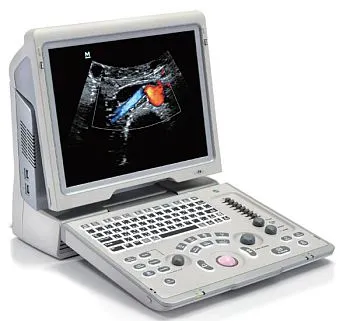

Клинические изображения

Система в большей степени предназначена для общих исследований, но также поддерживает объемные датчики и 3D/4D опции для визуализации плода.

Аппарат подойдет для общих исследований и первичной диагностики, врачей узких специальностей, приемных отделений, а также выездов на дом.